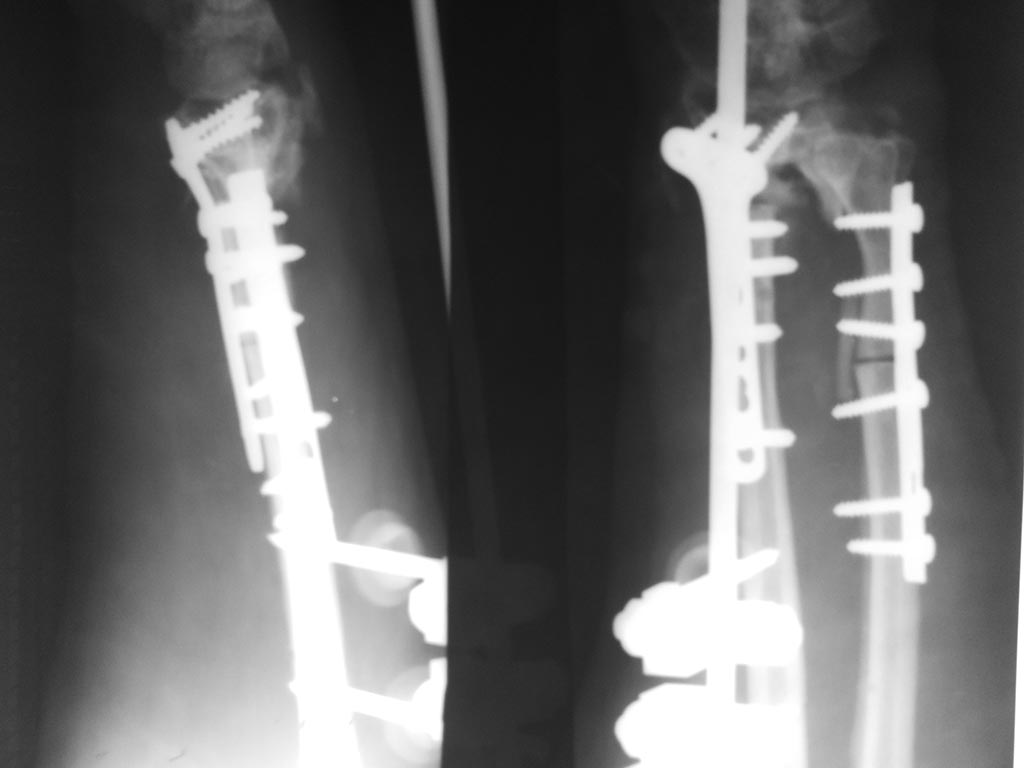

[Ortho] Неоартроз дистального метаэпифиза правой лучевой кости

Спасибо за помощь. Результаты оперативного лечения.